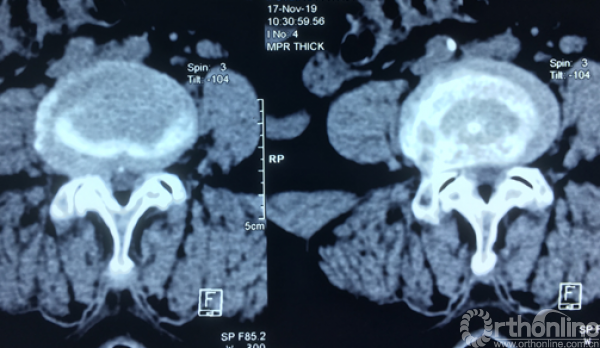

术前CT示:1.腰椎退行性变;2.L4椎体滑脱;3.腰椎管狭窄症;4.相应神经根硬膜囊受压。

术前CT